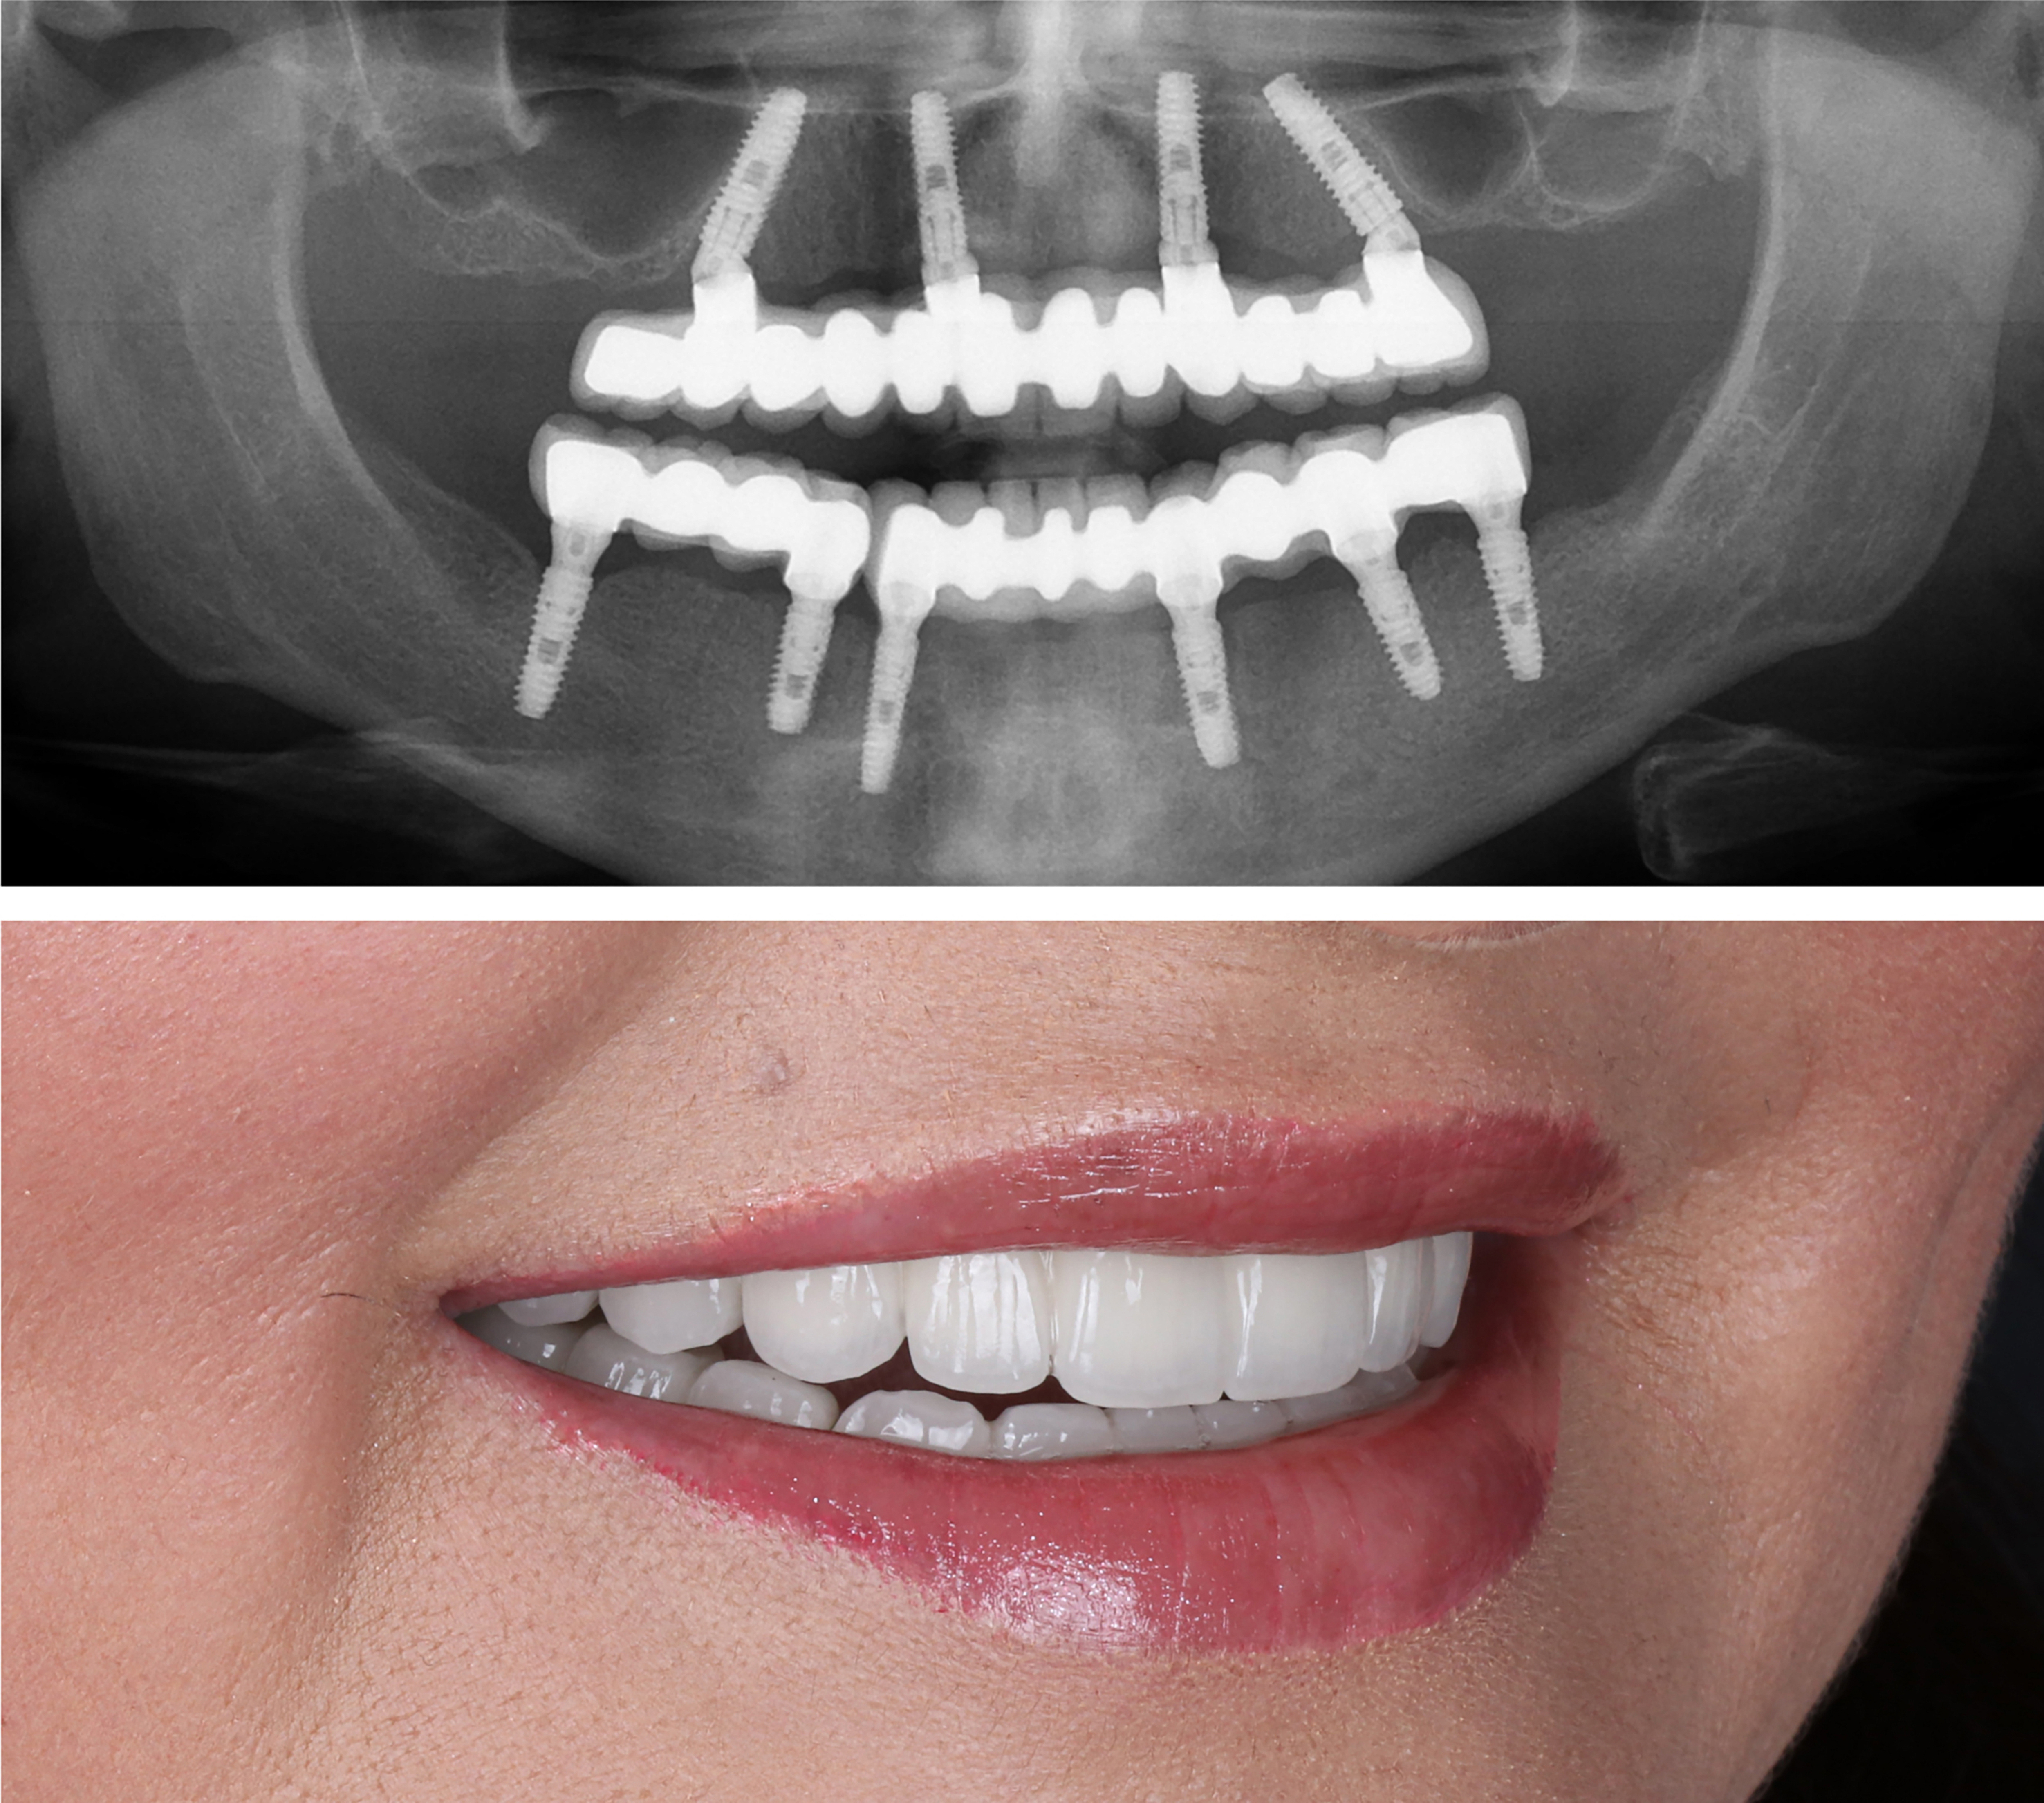

Example transformations achievable with dental implants

Regular Dentures VS Full Arch Dental Implants (Pros & Cons)

If you're missing a full row of teeth, you only have two treatment options to replace your smile - regular dentures or full arch dental implants. Many people mistakenly choose plastic dentures at first without thinking about the long term consequences.

The truth is that regular dentures accelerate jaw bone loss, cause facial sagging, and make it difficult to eat food comfortably. Full arch dental implants fix all of these problems and offer a high quality of life for the long run. Dental implants can easily last 40+ years without the need for replacement.

Regular dentures are known to need continual adjustment and replacement as they wear and tear over time.